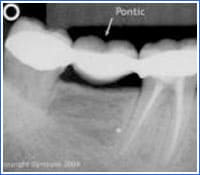

Bridges

Fixed bridges may replace one or more teeth and are connected to adjacent healthy teeth using a crown. A bridge cannot be removed. Teeth serving as retention for partial dentures or attachments for bridges may be: